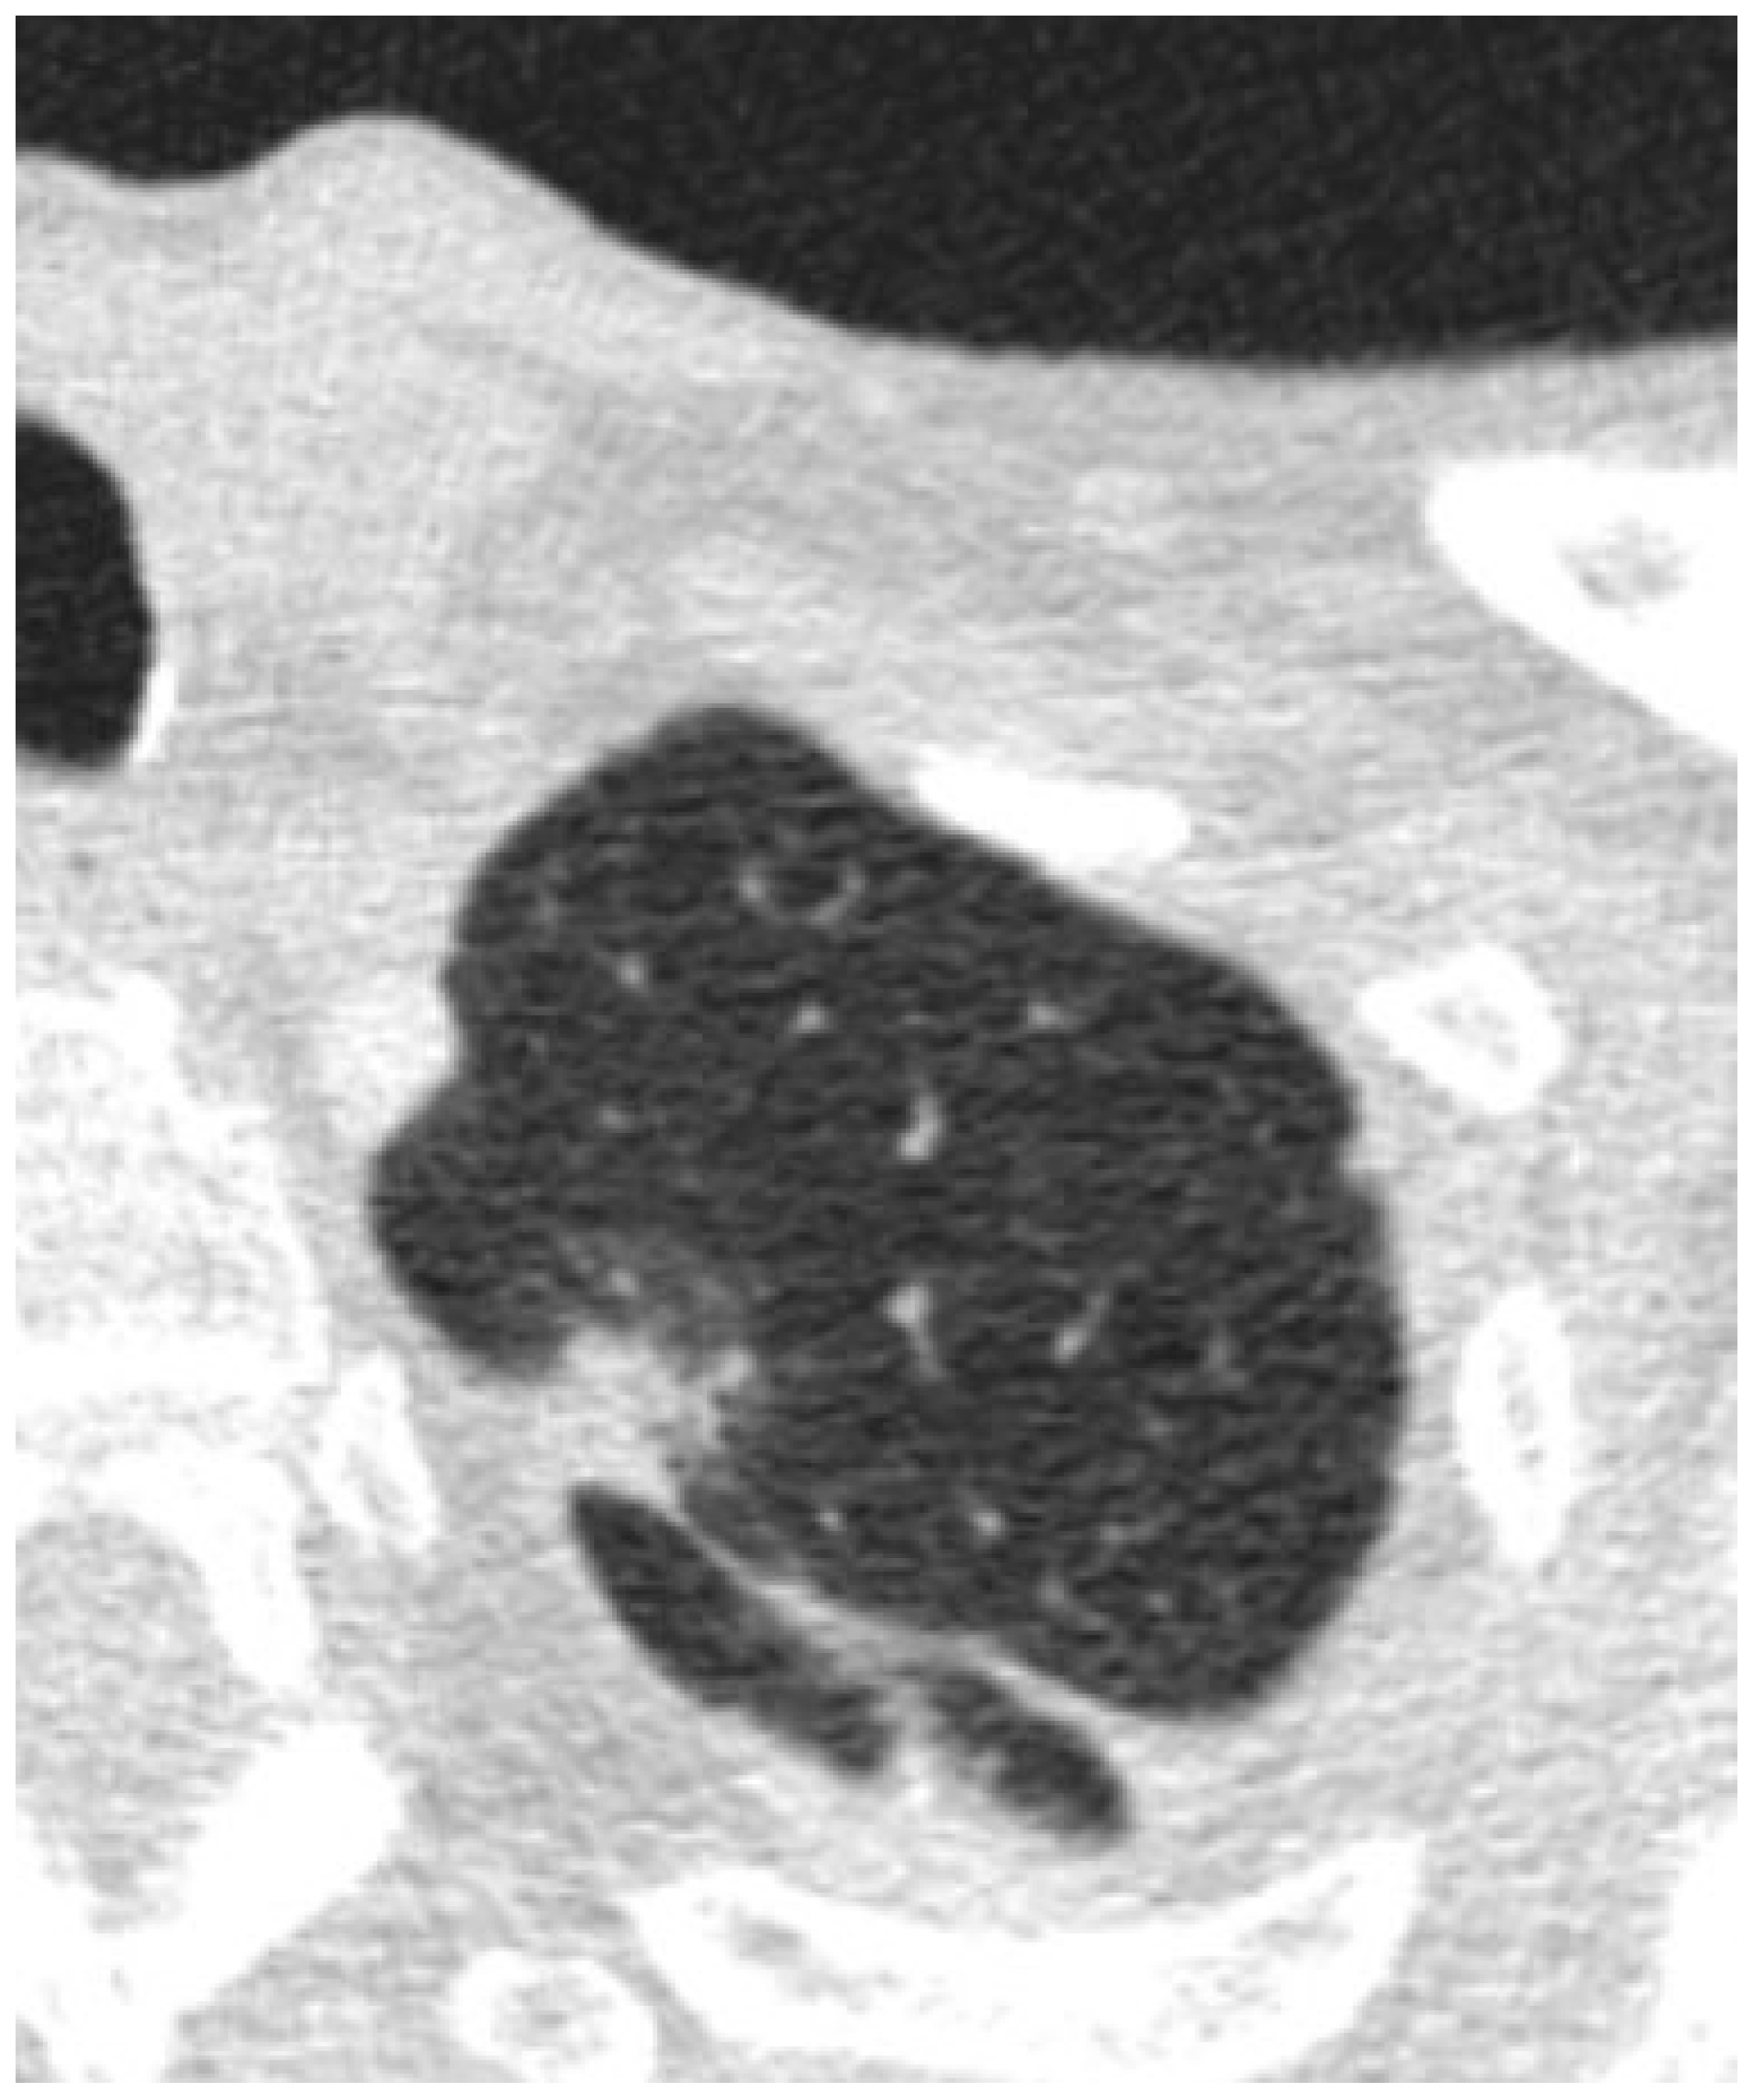

Figure 2.

Axial images depicting a nodule that was found to be AIS/MIA after resection.